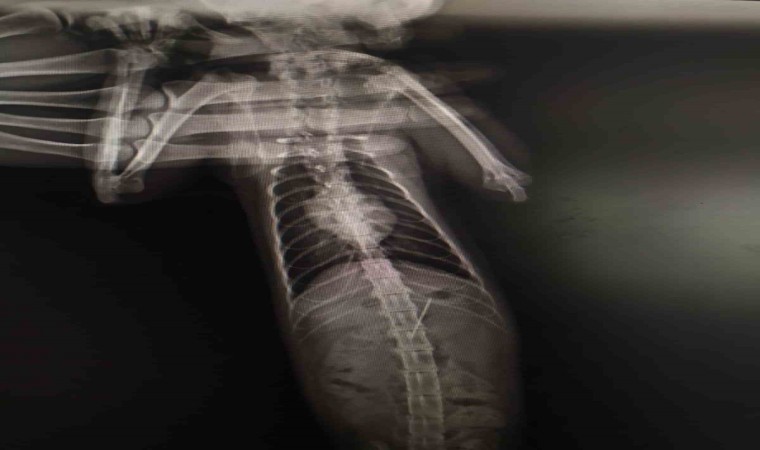

Bolu’da rahatsızlanarak veteriner hekime götürülen yaramaz kedinin midesinden, yuttuğu dikiş iğnesi çıktı.

Bolu’da kedisinin rahatsızlandığını fark eden bir kişi veteriner hekime başvurdu. Edinilen bilgiye göre, özel bir veteriner kliniğinde muayene edilen kedinin röntgeni çekildi. Kedinin midesinde dikiş iğnesi olduğu görüldü. Endoskopiyle dikiş iğnesi kedinin midesinden çıkartıldı. Bir süre veteriner kliniğinde müşahede altında tutulan kedi taburcu edildi.

Kedinin dikiş iğnesin yuttuğu öne sürüldü.